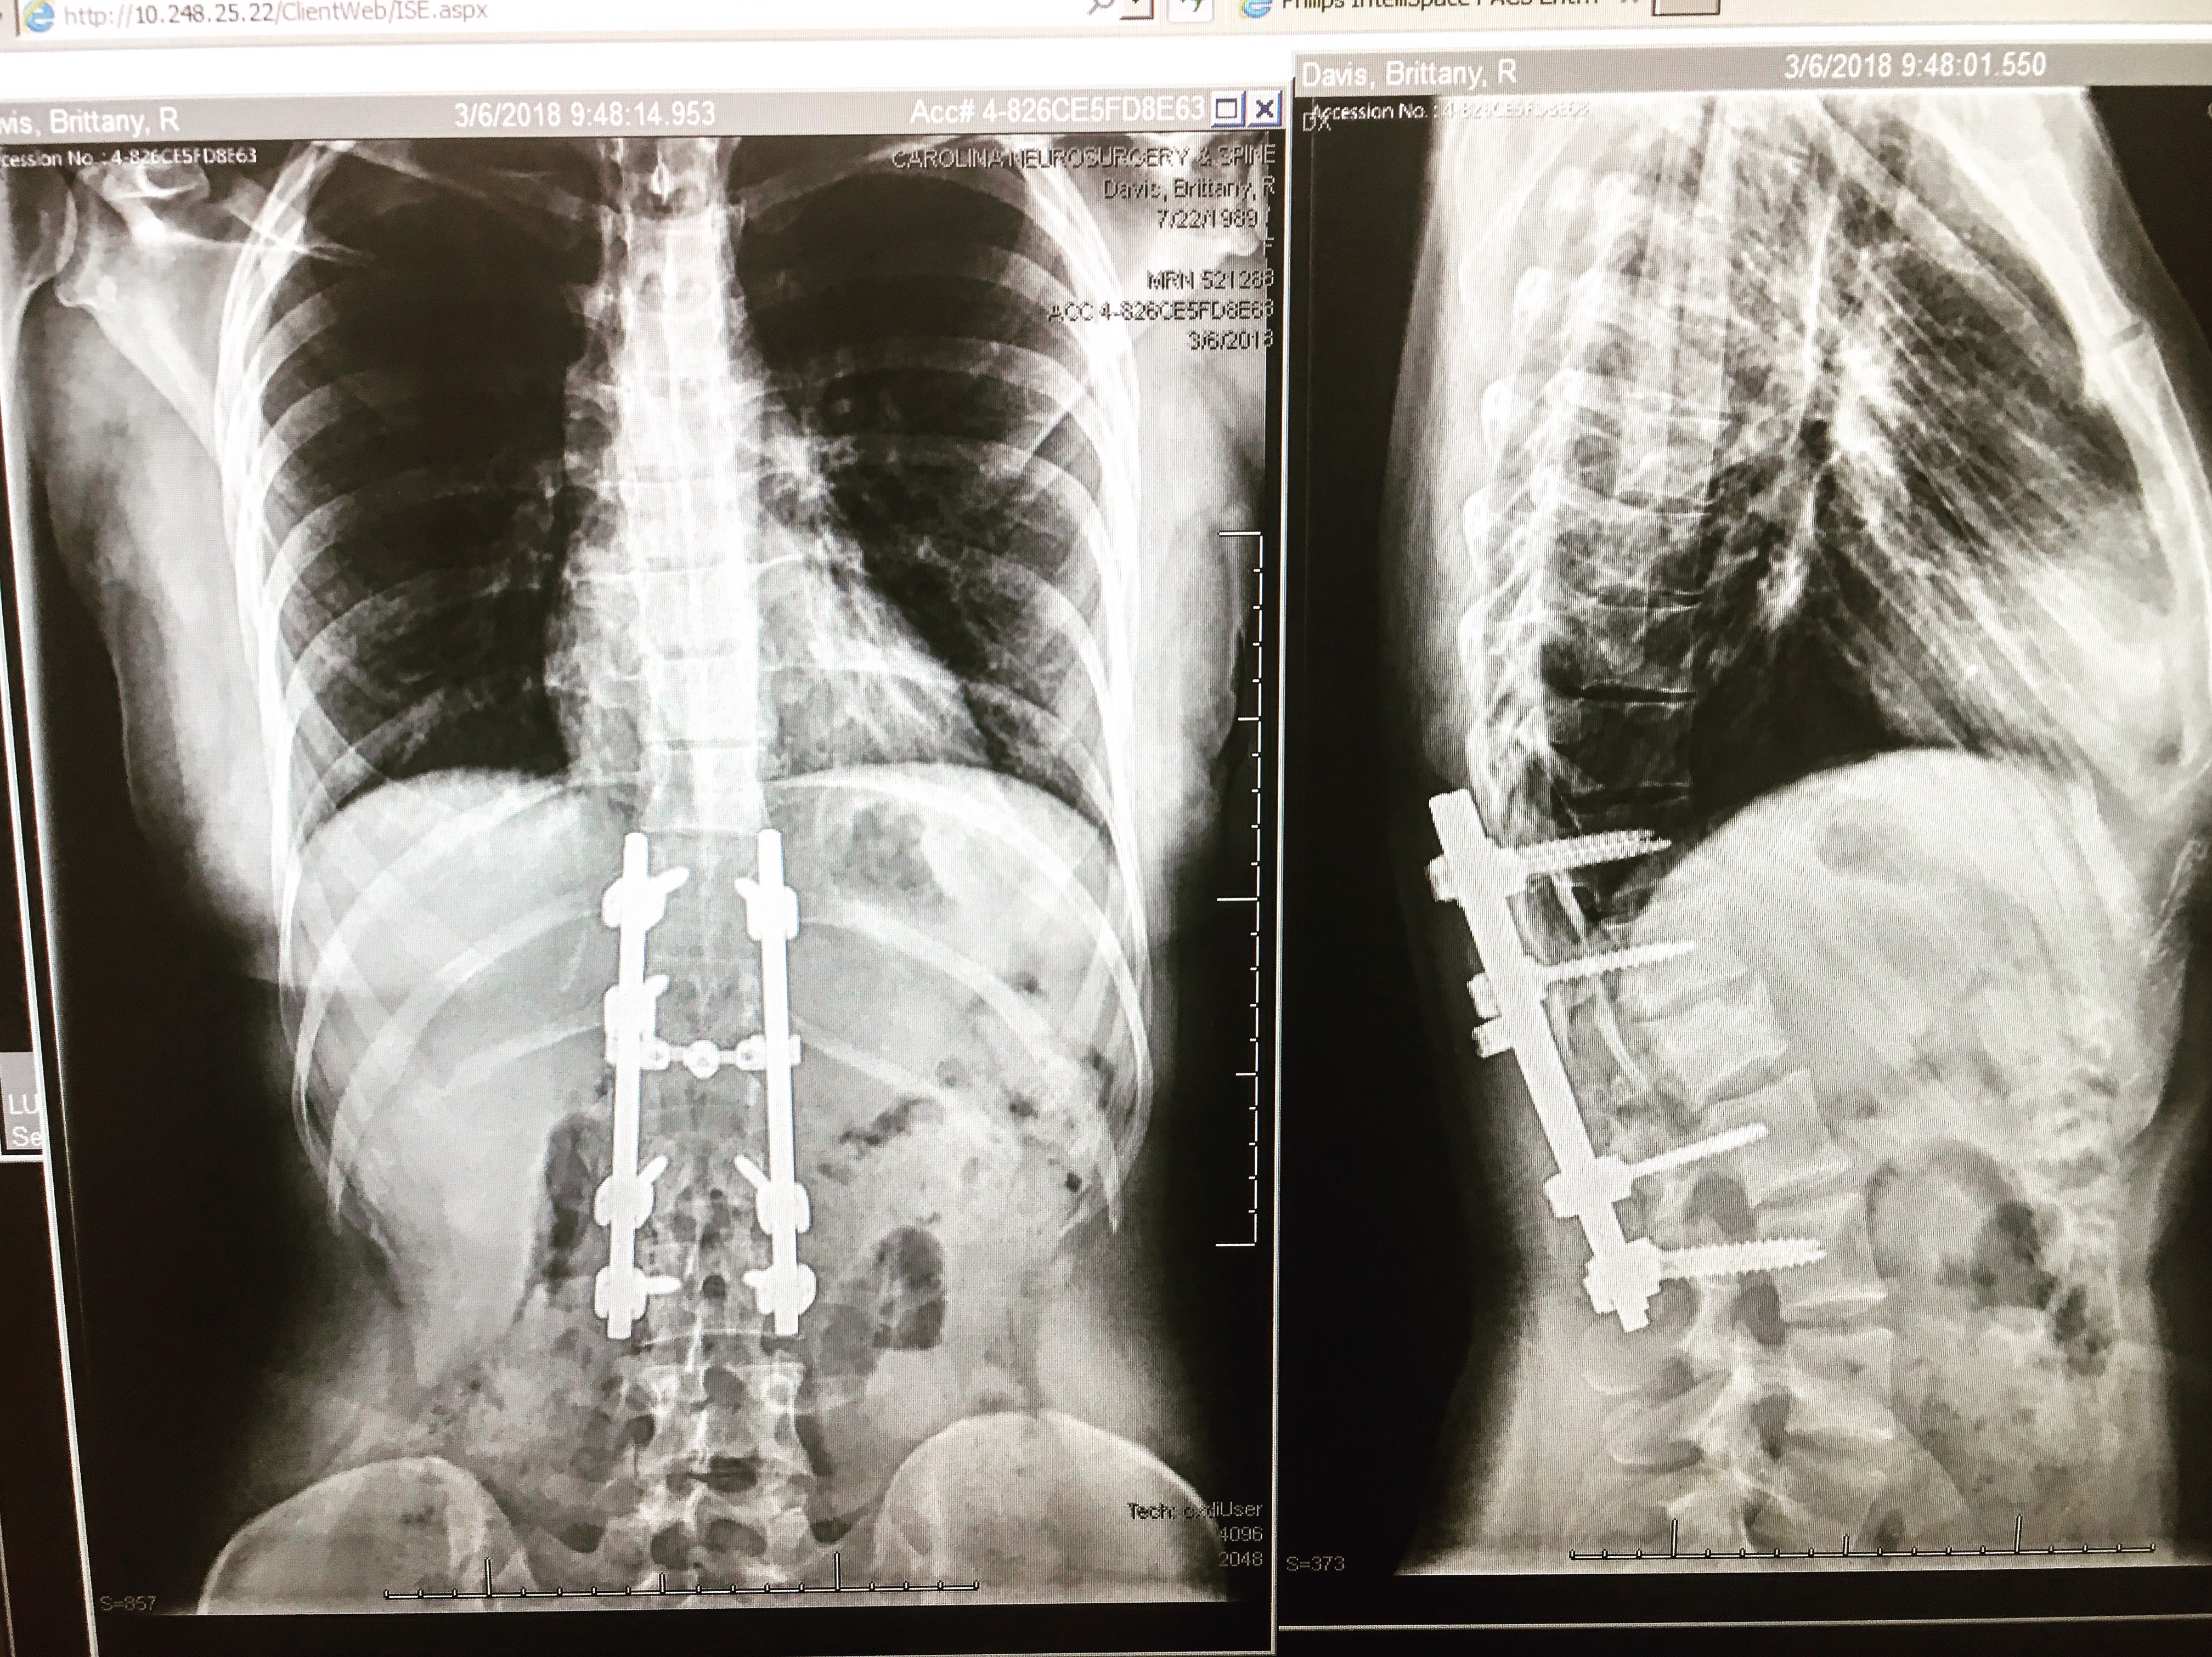

In a freak accident on March 29, 2017, I fell 40 feet; breaking the L1 vertebrae and the ulna and radius bones in my arm. Luckily, I don't remember the fall or much of what happened after. It all kind of felt like one of those surreal dreams where you wake up and think, 'Oh, thank God it wasn't real'. Except, I woke up and it was real. Laying there not being able to move my legs felt so strange! I was heartbroken at the thought that I would never be able to continue the sport I love: rock climbing. Climbing is who I am! It's my passion, my hobby, and my job as a rock climbing coach. The task of re-learning to walk hadn't even crossed my mind yet... I was so excited to return to climbing, regardless of how ugly it might be.